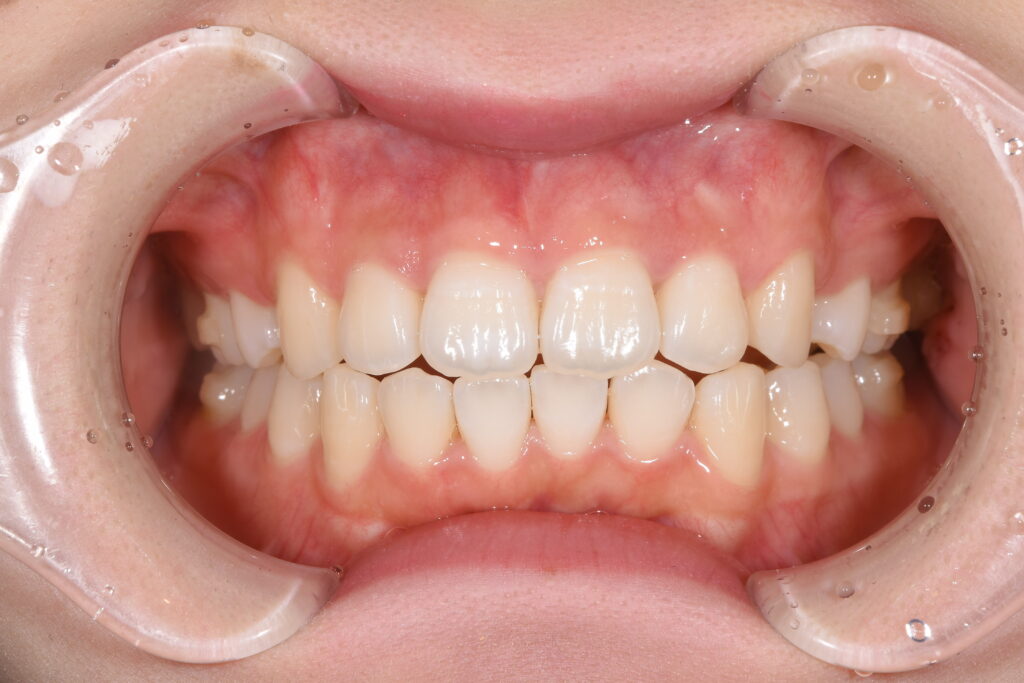

以下に治療1年後の写真です。

【矯正治療1年経過時】

今回の矯正治療は針金ではなく、インビザラインという透明なマウスピース矯正で行っており、一切針金は使用しておりません!

先生の考え方でインビザラインでは抜歯を行うと歯が並ばないという先生もいらっしゃいますが、このように当院では抜歯を行ってもインビザラインで綺麗な歯並びを獲得できます(^^)/